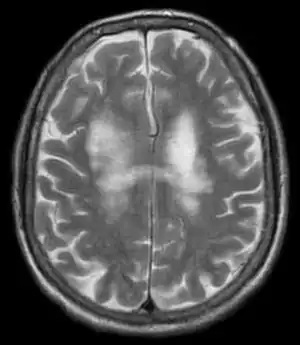

| T2-weighted MRI showing progressive multifocal leukoencephalopathy | |

PML is diagnosed in a patient with a progressive course of the disease, finding JC virus DNA in spinal fluid together with consistent white-matter lesions on brain magnetic resonance imaging (MRI); alternatively, a brain biopsy is diagnostic[6] when the typical histopathology of demyelination, bizarre astrocytes, and enlarged oligodendroglial nuclei are present, coupled with techniques showing the presence of JC virus.[17]

Characteristic evidence of PML on brain CT scan images are multifocal, noncontrast enhancing hypodense lesions without mass effect, but MRI is far more sensitive than CT.[17] The most common area of involvement is the cortical white matter of frontal and parieto occipital lobes, but lesions may occur anywhere in the brain, such as the basal ganglia, external capsule, and posterior cranial fossa structures such as the brain stem and cerebellum.[17] Although typically multifocal, natalizumab-associated PML is often monofocal, predominantly in the frontal lobe.[17]